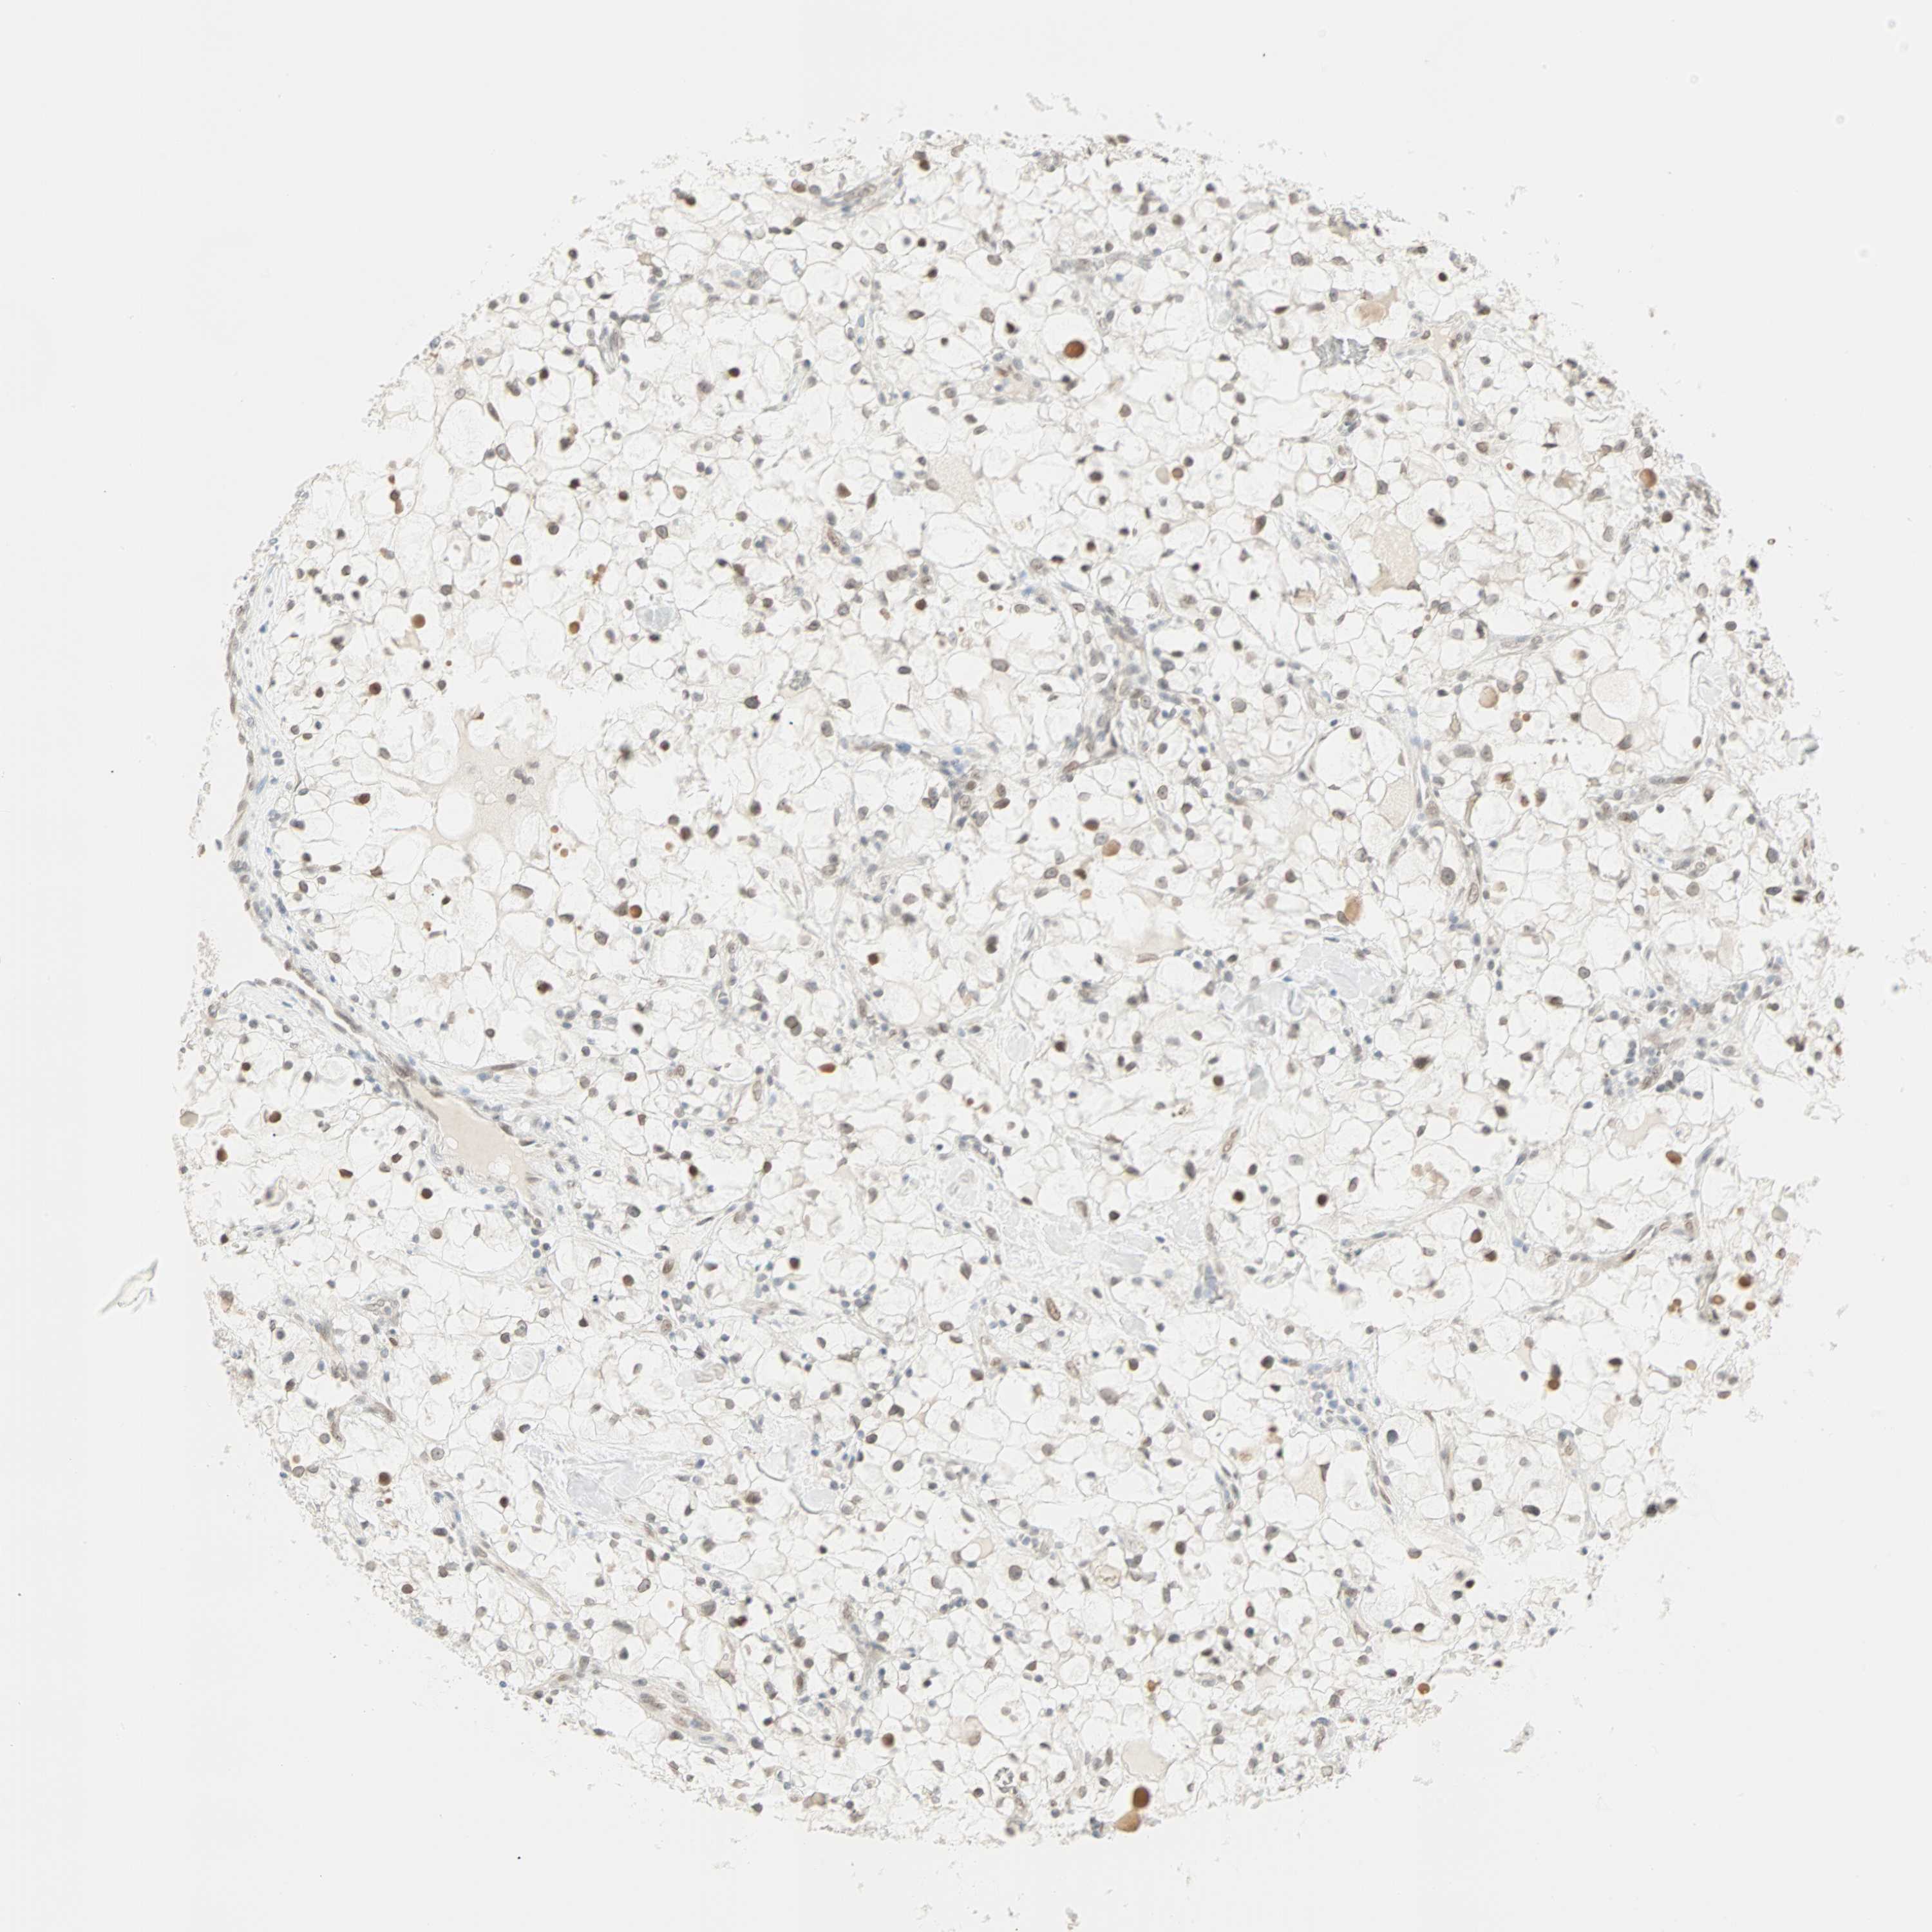

CANCER RENAL CANCER Show tissue menu

KICH TCGA KIRC TCGA KIRC VALIDATION KIRP TCGA PROTEIN RCC CPTAC PROTEIN EXPRESSION

BCAN is not prognostic in Kidney Renal Clear Cell Carcinoma (TCGA)